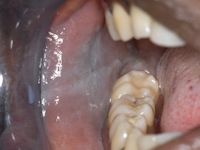

![Linea alba mucosa (click on photo to enlarge) [source: www.huidziekten.nl] Linea alba mucosa](../../../images/linea-alba-mucosa-2z.jpg) |

linea

alba mucosa |